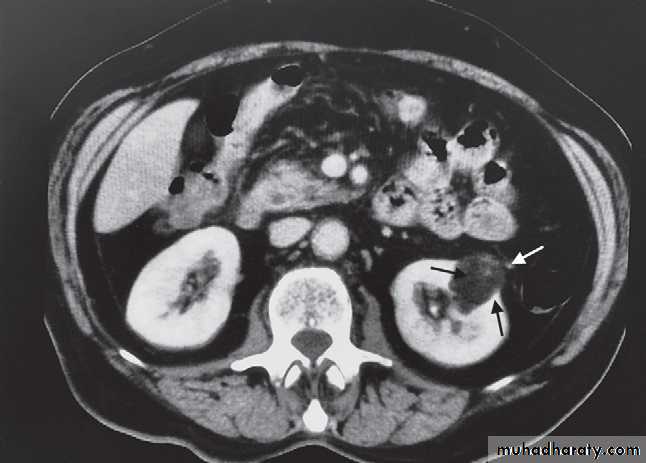

-Angiomyolipomas are usually incidental findings. They are benign tumours, which rarely cause problems, although, on occasion, they cause significant retroperitoneal haemorrhage.

At CT their fat content allows a confident diagnosis (Fig. 8.32b, c).

-Renal cell carcinomas are approximately spherical and often lobulated .With density similar to renal parenchyma or slightly less with often seen some areas of necrosis & calcification .